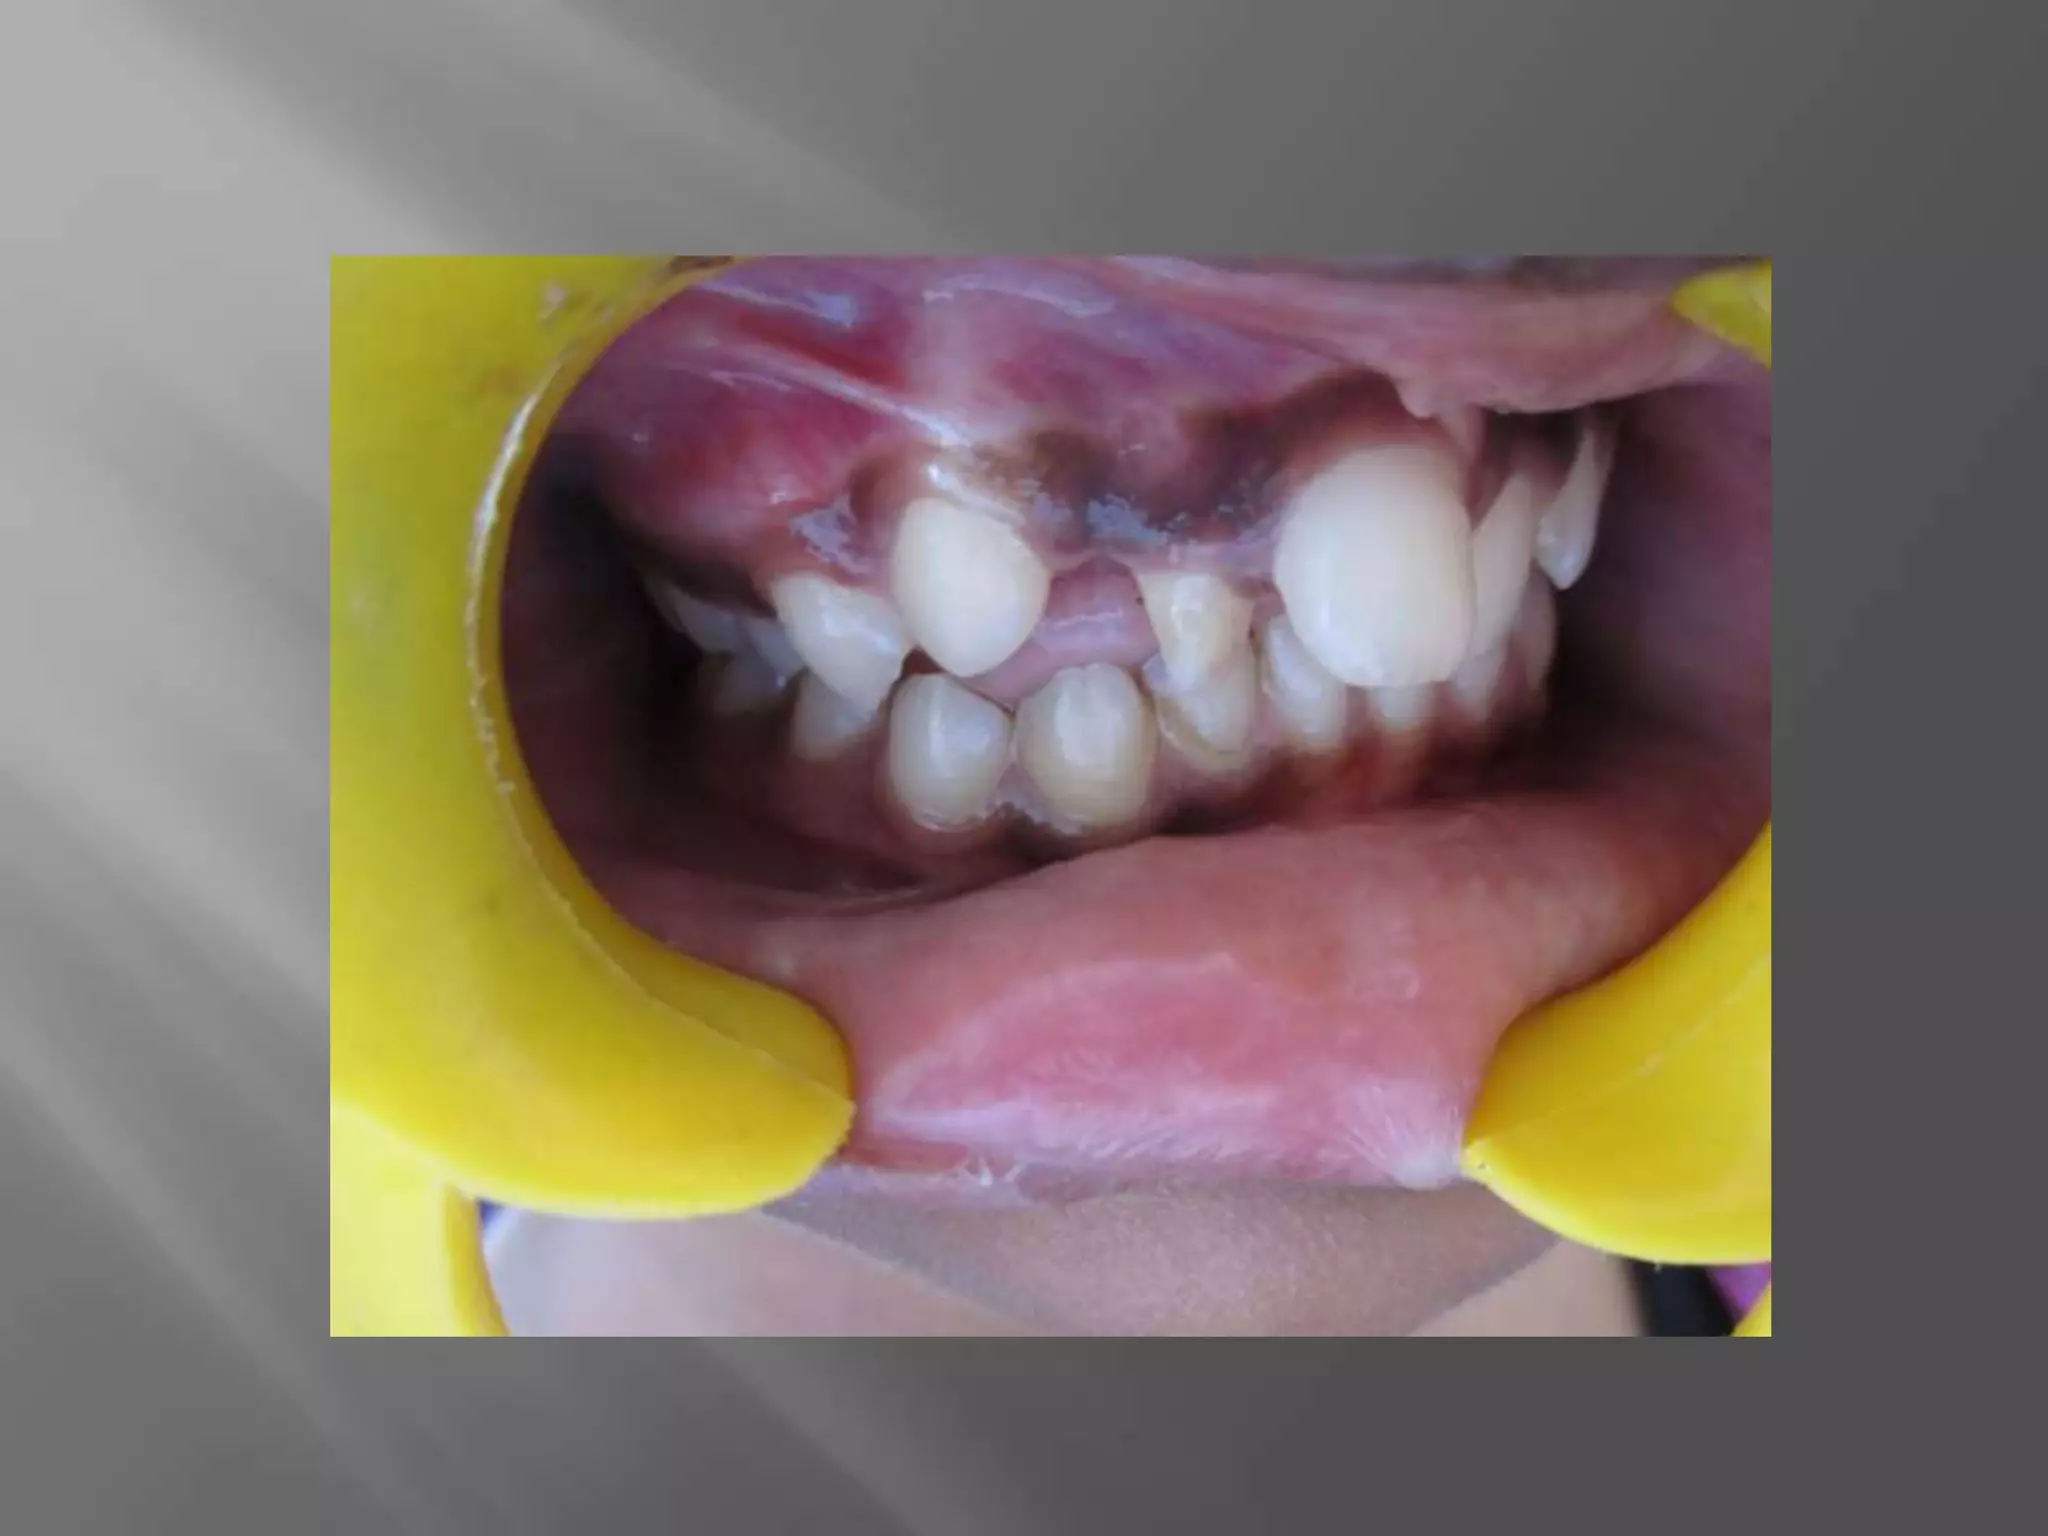

A 13-year-old female patient presented to the Department of Pedodontics with a chief complaint of irregularly arranged front teeth. Radiographs revealed a retained deciduous tooth in the right upper arch. Orthodontic correction was needed to rotate an anterior tooth into proper alignment.